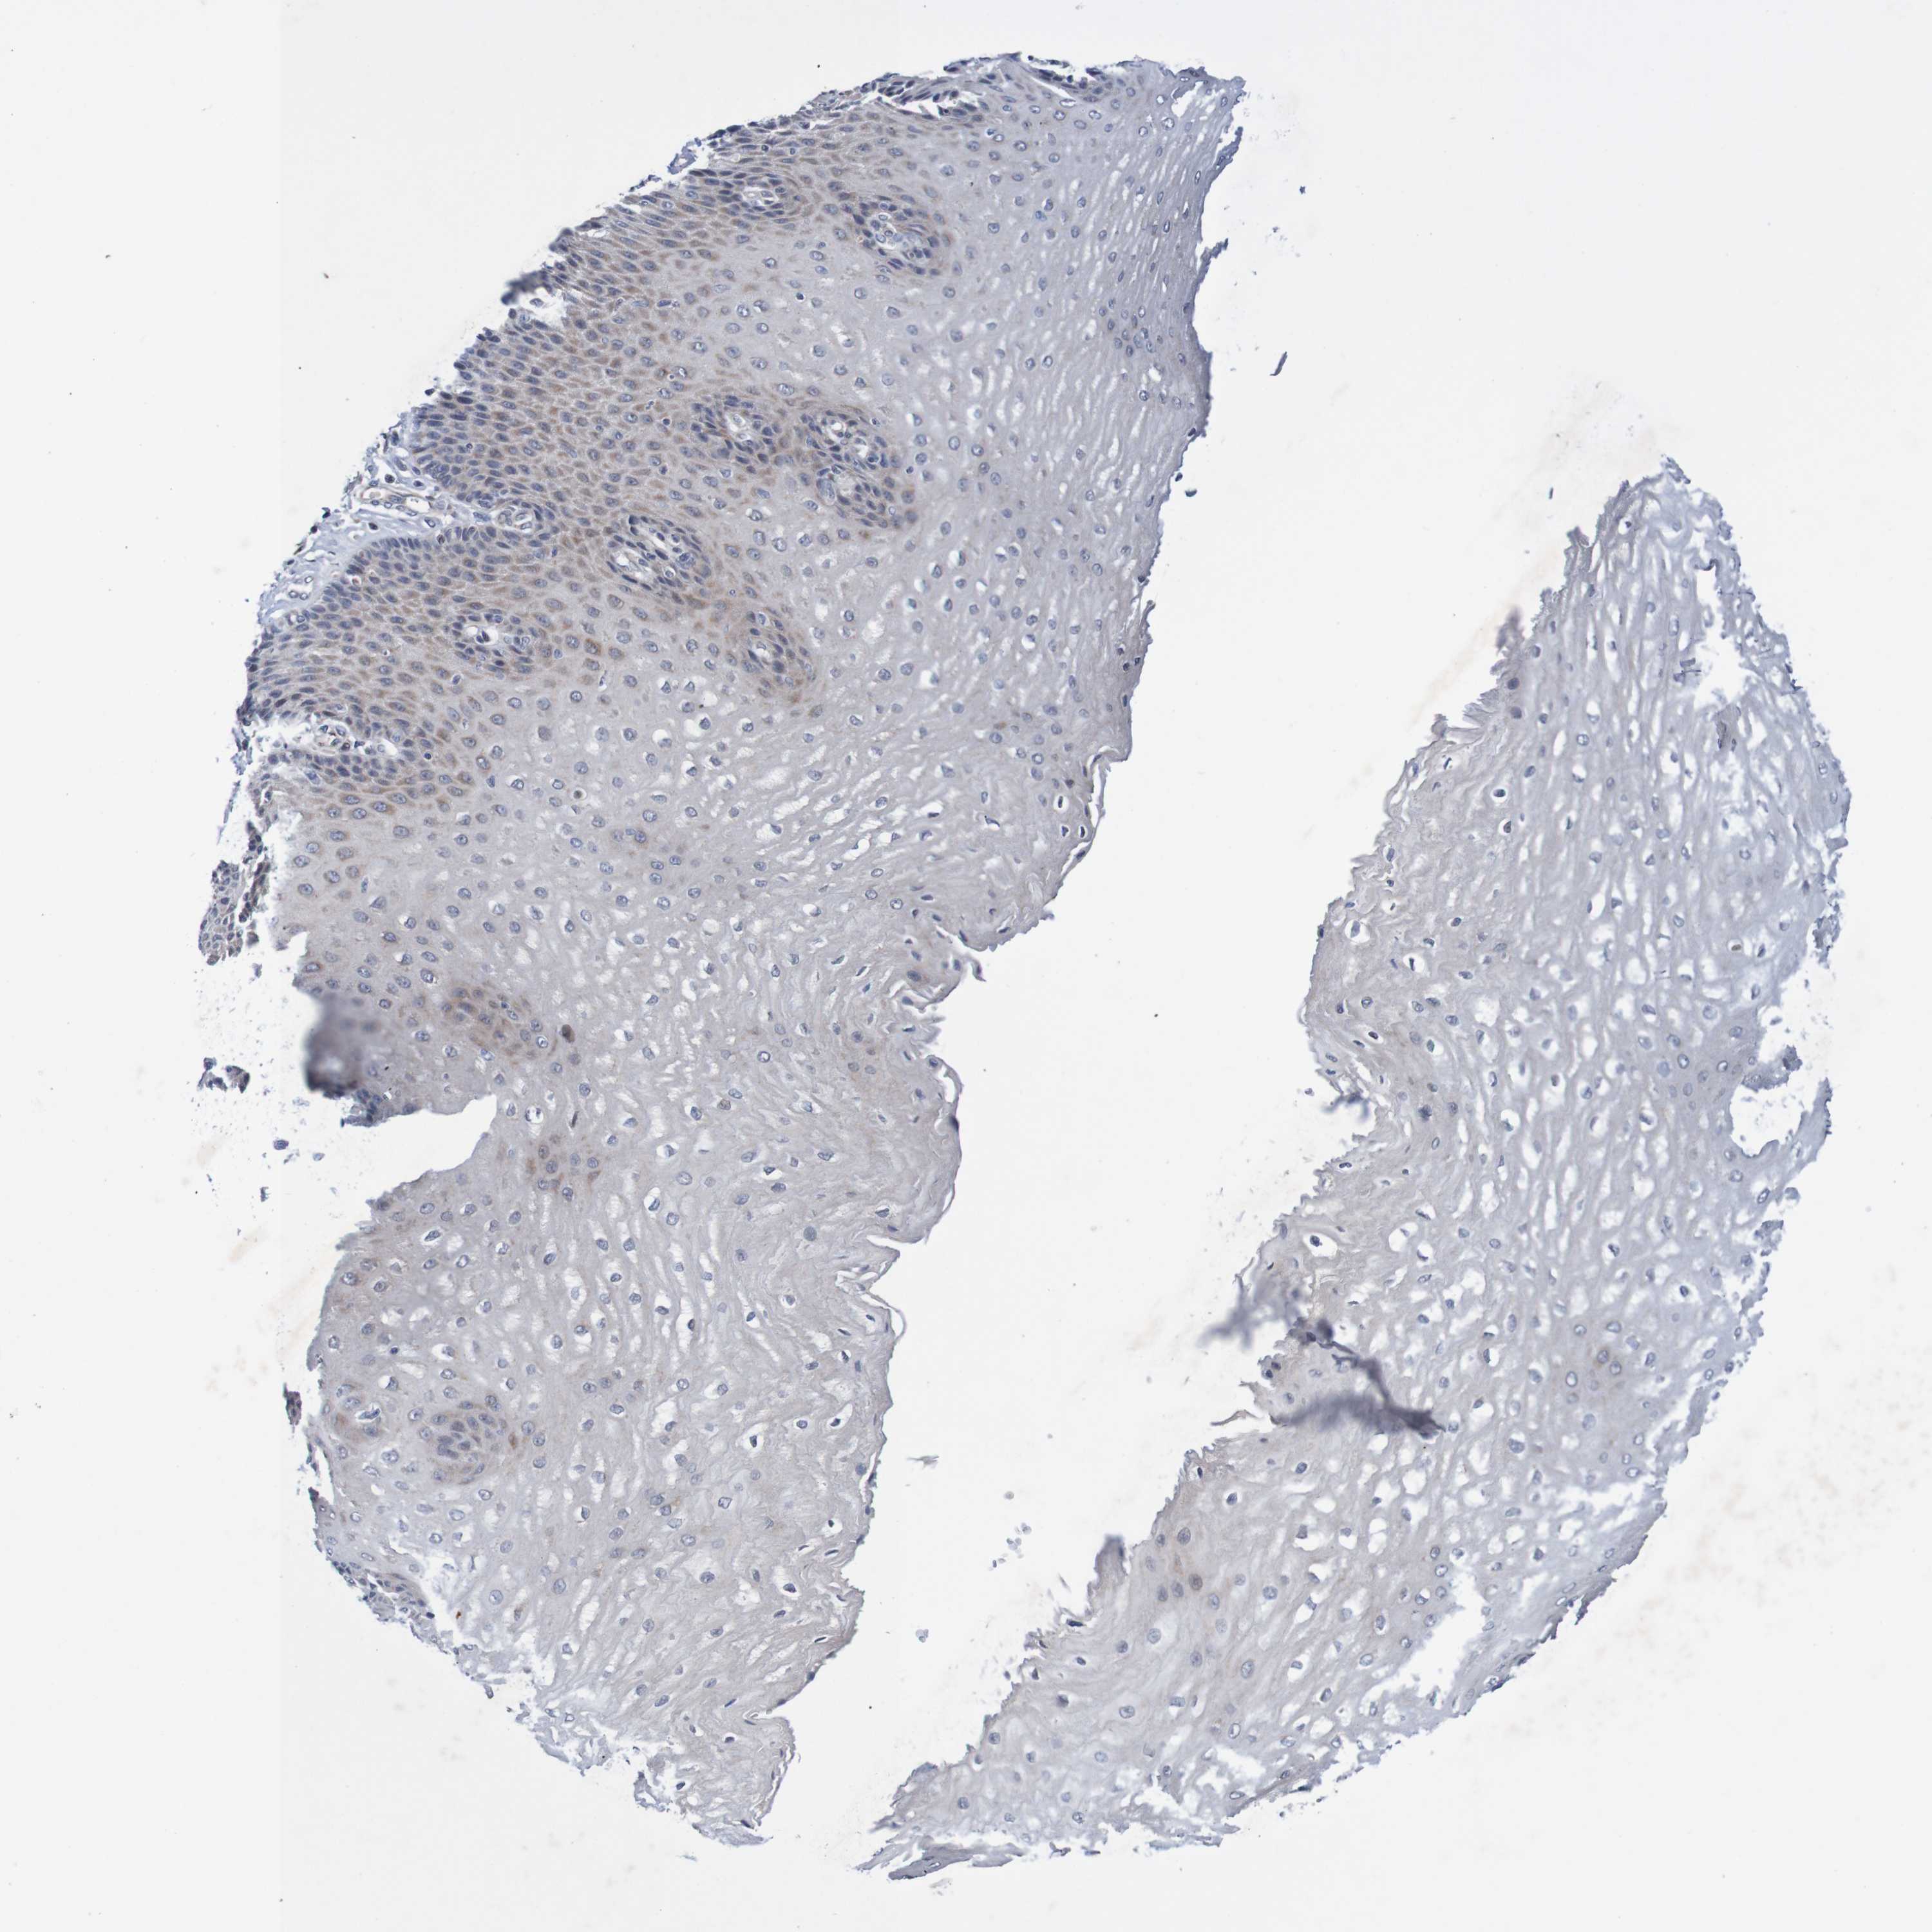

ESOPHAGUS - Antibody stainingi

Antibody staining in the annotated cell types in the current human tissue is reported as not detected, low, medium, or high, based on conventional immunohistochemistry profiling in selected tissues. This score is based on the combination of the staining intensity and fraction of stained cells.

Each image is clickable and will lead to virtual microscopy that enables deeper exploration of all samples and also displays staining intensity scores, fraction scores and subcellular localization as well as patient and tissue information for each sample.

Antibody HPA012058

Squamous epithelial cells Low